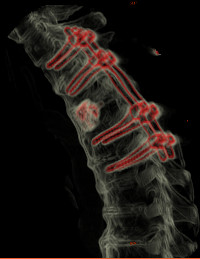

Tumeurs osseuses du rachis - Métastases et Fractures pathologiques

Généralités